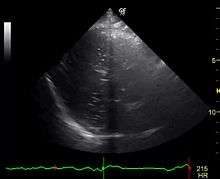

If an arterial gas embolism resulting from patent foramen ovale is suspected, an exam by echocardiography may be performed to diagnose the defect. In this test, very fine bubbles are introduced into a patient's vein by agitating saline in a syringe to produce the bubbles, then injecting them into an arm vein. A few seconds later, these bubbles may be clearly seen in the ultrasound image, as they travel through the patient's right atrium and ventricle. At this time, bubbles may be observed directly crossing a septal defect, or else a patent foramen ovale may be opened temporarily by asking the patient to perform the Valsalva maneuver while the bubbles are crossing through the right heart – an action which will open the foramen flap and show bubbles passing into the left heart. Such bubbles are too small to cause harm in the test, but such a diagnosis may alert the patient to possible problems which may occur from larger bubbles, formed during activities like underwater diving, where bubbles may grow during decompression.